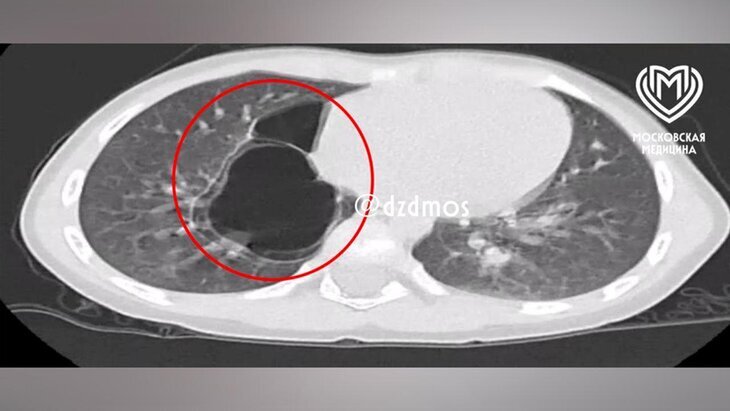

Фото: департамент здравоохранения Москвы

По итогам КТ врачи диагностировали юной пациентке кистозно-аденоматозную мальформацию легких – врожденный порок развития органов дыхательной системы, при котором легочная ткань замещается аномальной и происходит образование кист.

На рентгенографии медики обнаружили уплотнения в правом легком. С возрастом эти образования могут привести к дыхательной недостаточности и гиповентиляционному синдрому. Девочку начали готовить к операции.